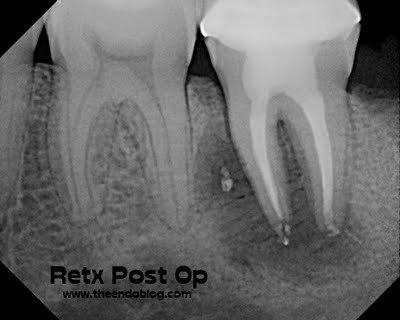

Retreatment completed.

4 month initial healing seen.